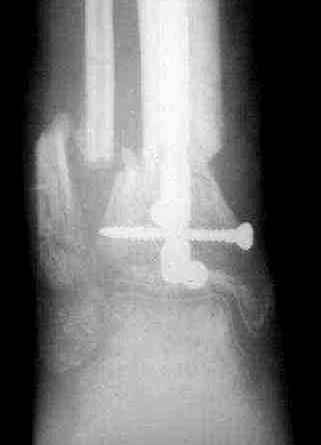

Пациент 19 лет, производственная травма, придавлен тяжелой плитой. Политравма (ISS 21).

1 - рентгенограмма (прошу прощения за качество) при поступлении;

2 - внешний вид голени;

Произведено ПХО, acute shortening (5 см), фиксация стержневым аппаратом Hoffman.

3,4 - через 4 недели наложен спице-стержневой аппарат, произведена остеотомия большеберцовой кости в верхней трети, раны зажили, проводилась дистракция в аппарате.

5, 6 - через 2,5 мес после травмы выполнен закрытый остеосинтез блокируемым штифтом.

7, 8, 9, 10, 11 - через 8 мес после травмы перелом сросся.

Пациент ходит без дополнительной опоры, не хромает (видеоролик выложил сюда

http://rapidshare.com/files/14134274/Patient_B.AVI.html, вес 892 кб).